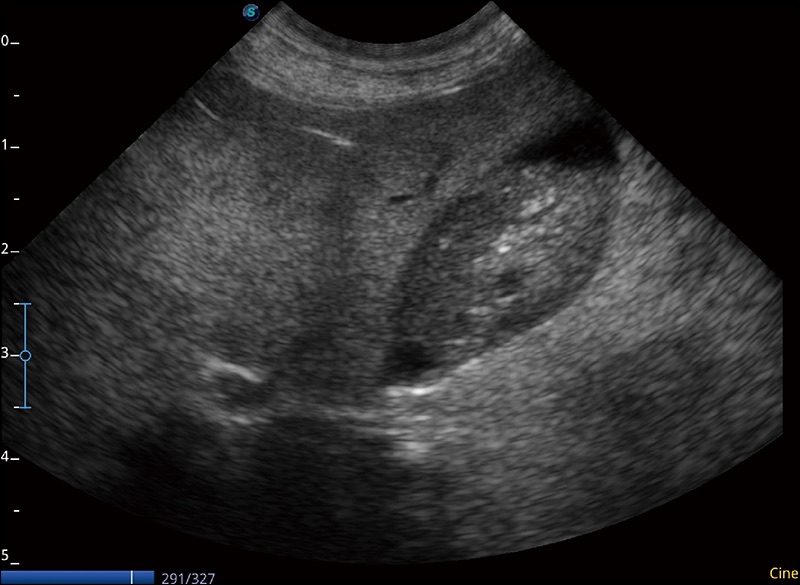

α1

精致轻巧 性能迅捷

α1卓越的图像质量和便捷的工作流程,使每位宠物医生都能轻松扫查。其全面的兽用应用功能和紧凑型的结构设计,可以满足动物检查的多种需要。专业的预设检查模式和多领域测量软件包有助于为不同类型的动物提供检查, 让宠物医生能够出色的完成工作。